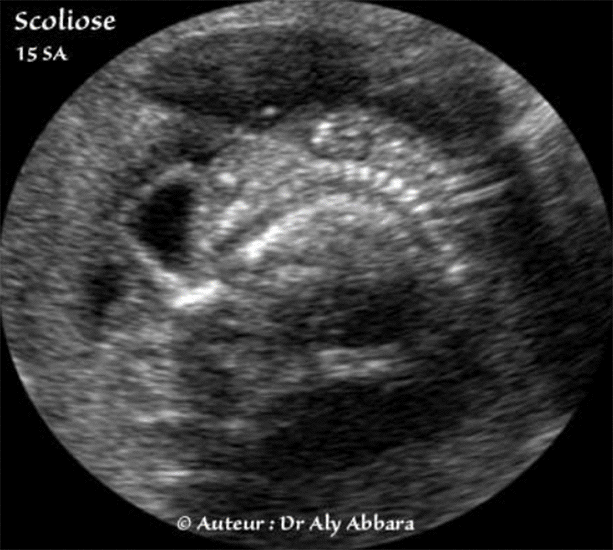

Scoliose (courbure latérale constante de la colonne vertébrale - Foetus âgé de 15 SA

• Image échographique montrant une scoliose importante (courbure ou incurvation latérale anormale de la colonne vertébrale) chez un fœtus âgé de 15 SA et présentant par ailleurs les autres anomalies anatomiques caractérisant la séquence polymalformative du cordon court, à savoir :

un cordon très court, une large célosomie adhérant, ainsi le reste du tronc, à la face fœtale du placenta, puis des adhérences amniotiques étendues entre le tronc fœtal et l'amnios du sac ovulaire.

Parmi les autres anomalies associées on observe aussi la présence d'une exencéphalie avec une dysmorphie faciale majeure, des anomalies des extrémités supérieures par compression et enfin, des pieds bots.

La scoliose importante s'explique par l'adhésion latérale du tronc fœtal au placenta.